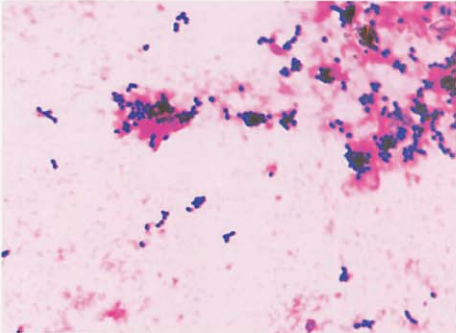

(一) 溶血孪生球菌形态与染色

革兰阳性球菌,但易染成革兰阴性,呈肾形,成单或成对排列,多成对排列,也可四联状或短链状排列(图 3)。

图 3溶血孪生球菌纯培养镜下形态(革兰染色)